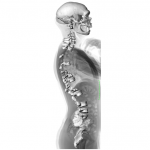

Reconstruction of the La Chapelle-aux-Saints Neanderthal spine superimposed onto the radiograph of a modern human

Martin Haeusler, University of Zurich